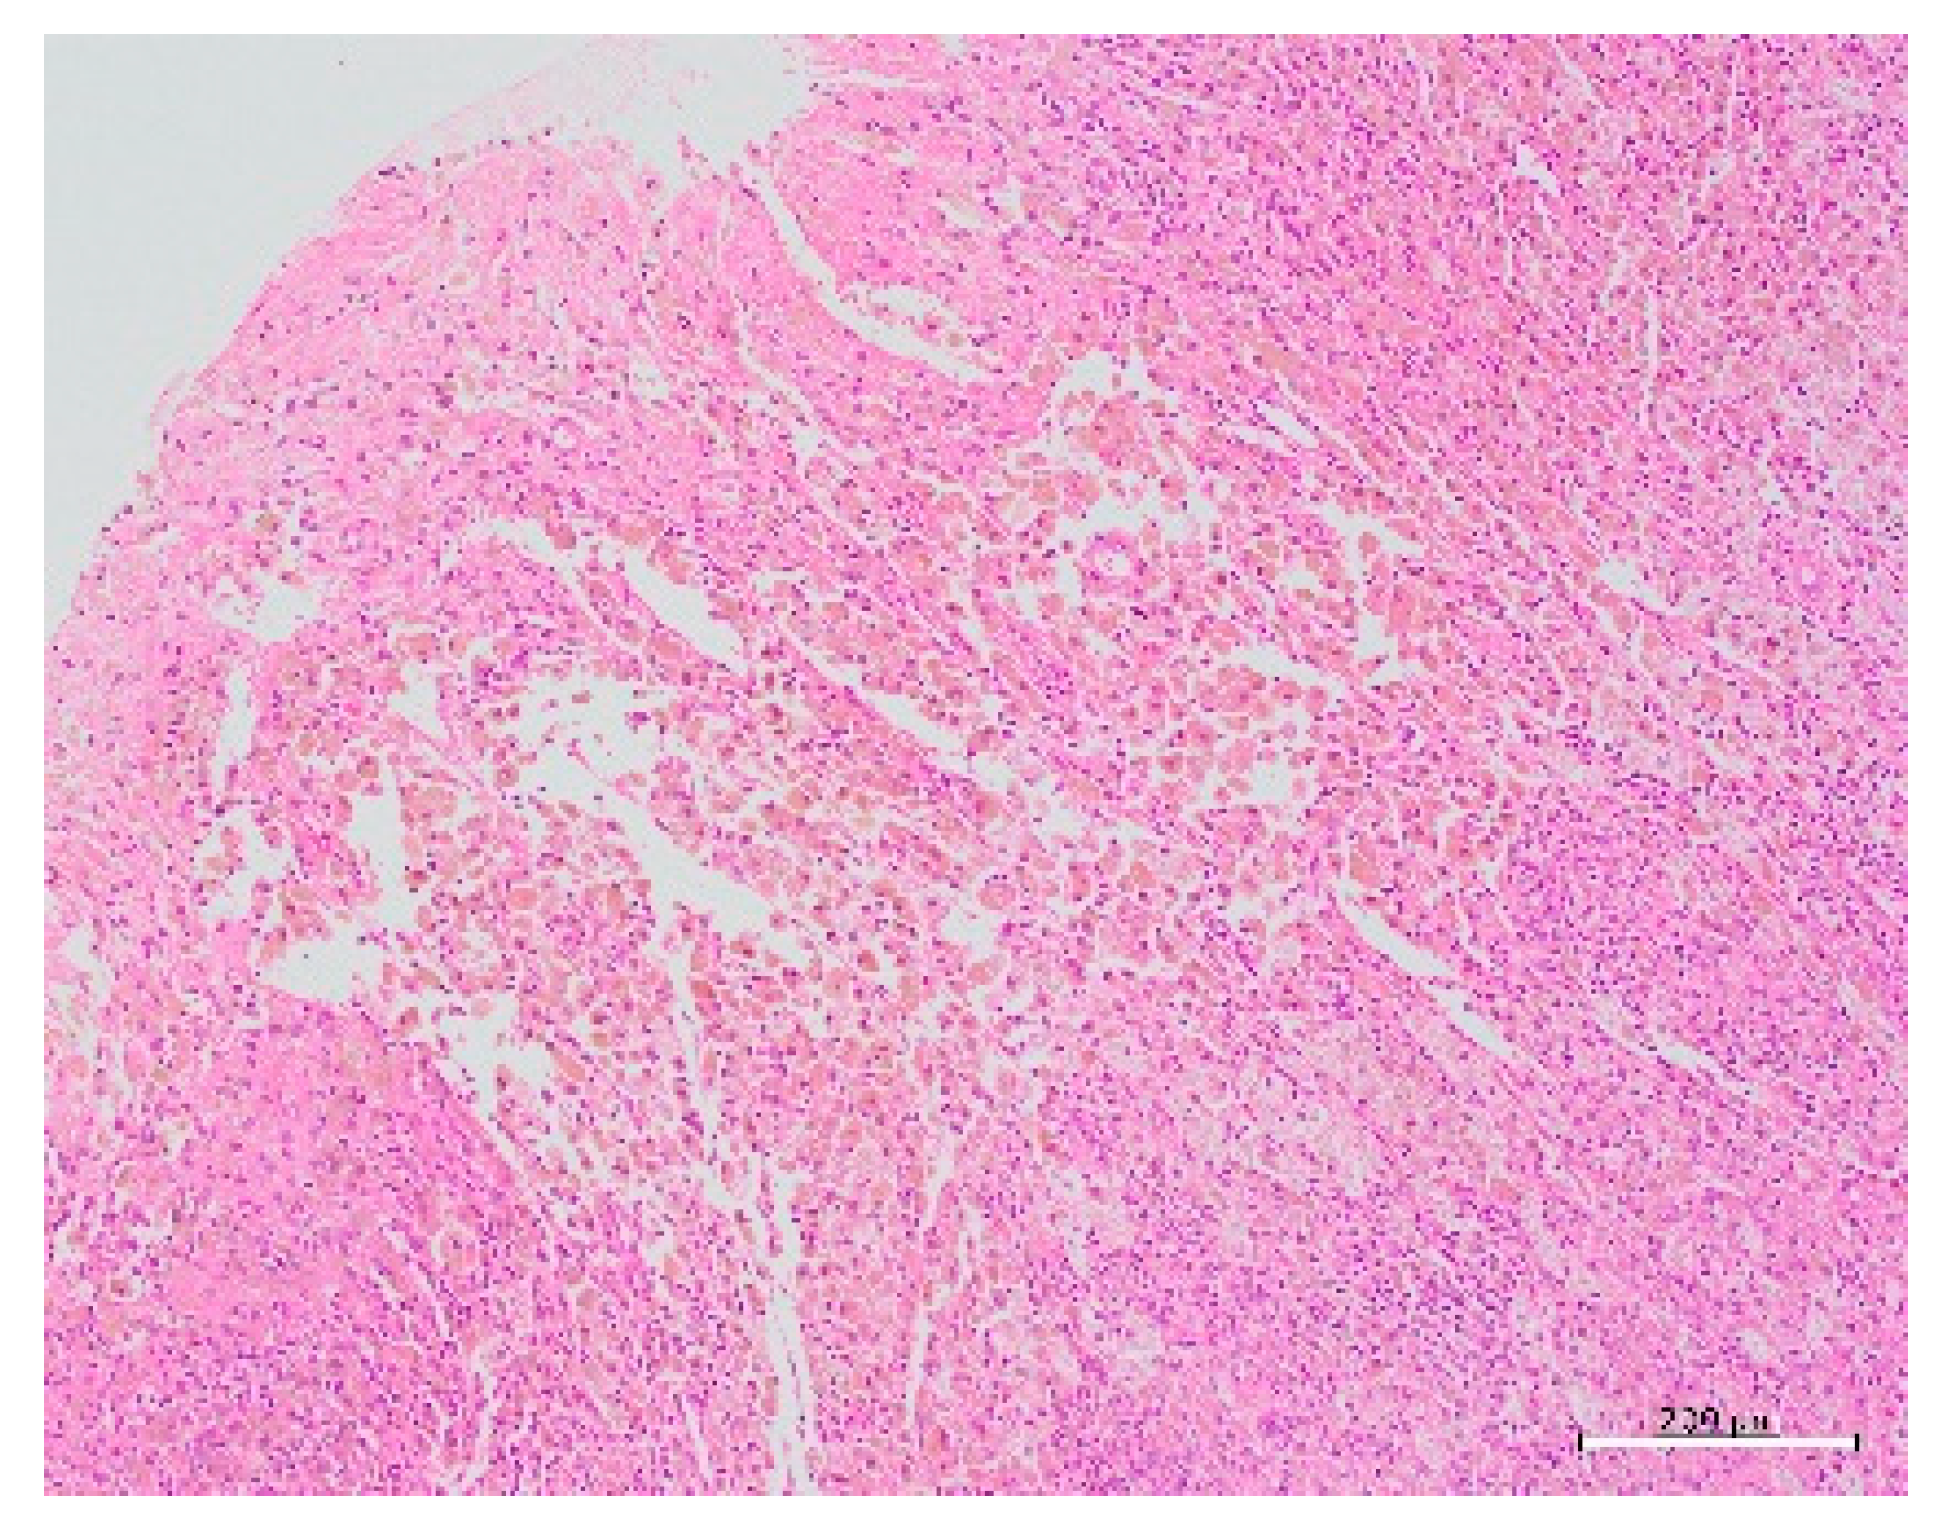

A 22-year-old nulliparous woman had a history of severe and worsening dysmenorrhea with cramps since the preceding 8 months, which was insufficiently relieved by a combination of non-steroidal anti-inflammatory drugs and oral contraceptive pills. She had severe dysmenorrhea and complained of non-cyclical chronic pelvic pain since she went through menarche when she was 13 years old. She visited our hospital and underwent an ultrasound examination, which revealed a 30-mm pelvic mass on the right side of the uterus, with dense echoes, and an extremely rich blood signal in the cyst wall (Figure 1). Subsequently, contrast-enhanced abdominal computed tomography (CT) revealed a cystic lesion measuring 3 cm in diameter, on the left wall of the uterine corpus (Figure 2). On pelvic magnetic resonance imaging (MRI), the T1-weighted image revealed a hyperintense cyst on the left side of the uterus, and the T2-weighted image showed a normal uterine cavity and a hypointense lesion on the left side of the myometrium. The cyst did not exhibit diffusion restriction in diffusion-weighted images or the Apparent Diffusion Coefficient Map (Figure 3). No urogenital anomalies were noted on CT or MRI. The bilateral adnexa appeared normal. We advised laparoscopic surgery with possible resection of the cystic mass to relieve persistent pelvic pain. The patient provided informed consent prior to the procedure and was admitted to the hospital the day before the procedure. The bowel was prepared using a sodium phosphate solution enema. Antibiotic prophylaxis was administered at the time of anesthesia induction. Laparoscopic surgery was performed under general anesthesia. Carbon dioxide pneumoperitoneum with a pressure of 10 mmHg was created using a Veress needle at the umbilicus. Peritoneal entry was achieved by direct trocar insertion at the umbilicus. Three accessory port techniques were used: two in the suprapubic area and one in the lower quadrant lateral to the right inferior epigastric artery. Laparoscopy revealed a 3-cm uterine mass arising from the left lateral uterine wall extending towards the left broad ligament. Before cyst removal, diluted epinephrine (1:1,000,000) was injected into the posterior wall of the uterus using 23-gauge suction needles (Hakko Medical, Nagano, Japan). The serosa was incised using an ultrasonic scalpel (Harmonic Scalpel; Ethicon Endo-Surgery, Cincinnati, OH, USA). After incising the posterior uterine wall, adenomyotic foci were identified, and only the adenomyotic cysts were enucleated with tactile confirmation of the boundaries between the adenomyotic tissue and normal muscle layer using scissor forceps. The cyst was gently removed without rupturing. The cyst was placed in Morsafe™ (Balmer Médical, SA, Switzerland) and morcellated using a Rotocut G1 morcellator (Karl Storz GmbH & Co. KG, Tuttlingen, Germany). Inside the cyst, chocolate-colored fluid was visible. The myometrial defect was closed in two layers using 0 PDS II sutures (Ethicon Japan, Tokyo, Japan). Finally, the operated uterus was wrapped with oxidized regenerated cellulose (Interceed; Ethicon, Japan, Tokyo, Japan) to prevent adhesion to adjacent tissues, after washing the pelvic cavity with copious amounts of saline. The surgery was completed in 69 min with minimal blood loss. The specimen weighed 14 g (Figure 4). The detailed procedure of the laparoscopic surgery is presented in the video (Supplementary Materials). Postoperative pathology revealed myometrial cysts and bleeding on the inner wall. Microscopic examination confirmed the presence of endometriotic cysts (Figure 5). Based on the histopathology results and laparoscopy findings, cystic adenomyosis was diagnosed postoperatively. The patient was discharged 4 days after the surgery. One month after the surgery, postoperative transvaginal ultrasonography revealed complete resolution of the myometrial cystic lesion and restoration of the normal anatomy. She no longer experienced dysmenorrhea. Preoperatively, the severity of dysmenorrhea was 97 on a visual analog scale ranging from 0 (no pain) to 100 (extremely severe pain), whereas the postoperative score was 2.

Figure 5. Histopathological picture showing glandular tissue with round nuclei and interstitial tissue scattered in islands within the tissue.